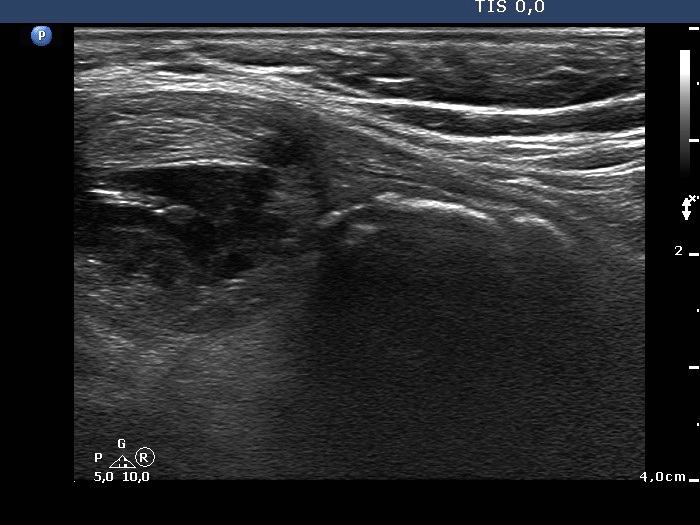

Benign hyperplastic nodule (histological diagnosis) - case 80

There were multiple foci of coarse calcification in this case. Note that acoustic shadowing is complete only at the edges of the lesions.